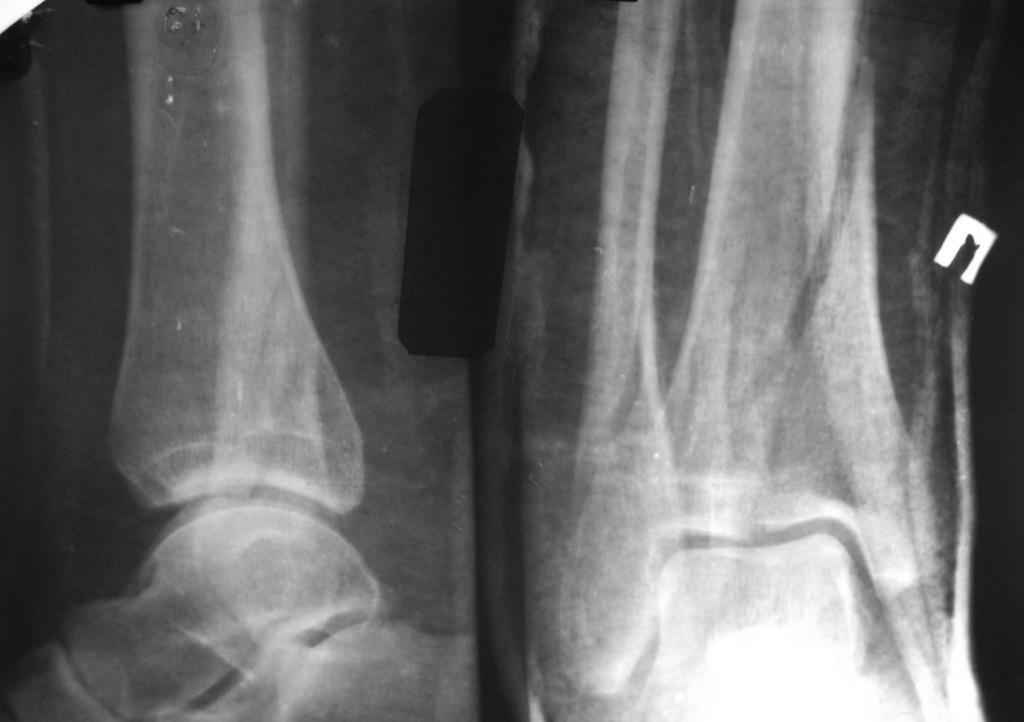

перелом пилона. тактика лечения

помогите определиться с тактикой лечения даного перелома пилона

Больной, 46 лет. Травма 27.08.08. При поступлении, в травмпункте была проведена блокада места перелома, иммобилизация гипсовой повязкой. Единого мнения по поводу дальнейшего лечения пока нет. Просьба высловиться по поводу возможностей лечения даного перелома, вообще возможности оперативного лечения. Спасибо за ответы.

прошу прощения за то, что забыл приложить снимки

открытая репозиция и фиксация

- малоберцовая - 3.5 мм 1\3 трубчатая пластина.

- большеберцовая - масса вариантов, начиная с множественных шурупов без пластины и заканчивая locking plate для дистальной тибии